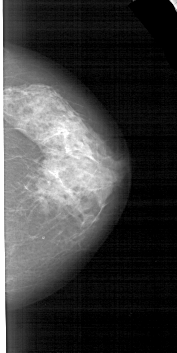

A_1553_1.RIGHT_MLO

RIGHT_MLO LINES 5146 PIXELS_PER_LINE 2611 BITS_PER_PIXEL 12 RESOLUTION 43.5 NON_OVERLAY